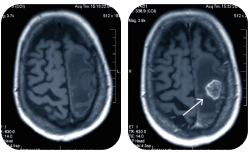

• КТ головы

КТ головы

Компьютерная томография головы в Клинике Эксперт в Липецке -  это метод медицинского обследования. Его назначают, когда необходимо определить состояние костей и сосудов головного мозга.